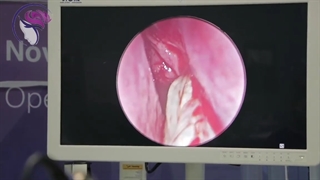

۱۰ روز بعد از جراحی همزمان جراحی زیبایی بینی و سینوزیت